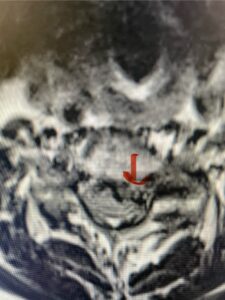

In this next case, this patient is a 47 year-old female who presents with intractable low back pain with severe pain, numbness, and weakness in the right lower extremity that had gotten progressively worse over a year. The patient had failed conservative management including physical therapy and epidurals. She was noted to have ⅘ weakness of plantar flexion. MRI demonstrated a large right L5-S1 disc herniation with severe compression of the descending right S1 nerve root (Fig 3). It was decided to perform a right L5-S1 hemilaminectomy for removal of the disc fragment and decompress the S1 nerve root. When you expose the disc, one must be certain to release any anterior adhesions to the nerve root in order to prevent a dural tear during retraction of the nerve root. It is also important to make sure during exposure and you finally encounter the dura after removing the ligamentum and fat, to make sure you are looking at the nerve root and not the main trunk of the thecal sac because if you don’t you can avulse or damage the nerve root if you retract the wrong structure.

Fig. 3a: Sagittal and axial T2-weighted lumbar MRI images demonstrating large right L5-S1 disc herniation (red arrows)